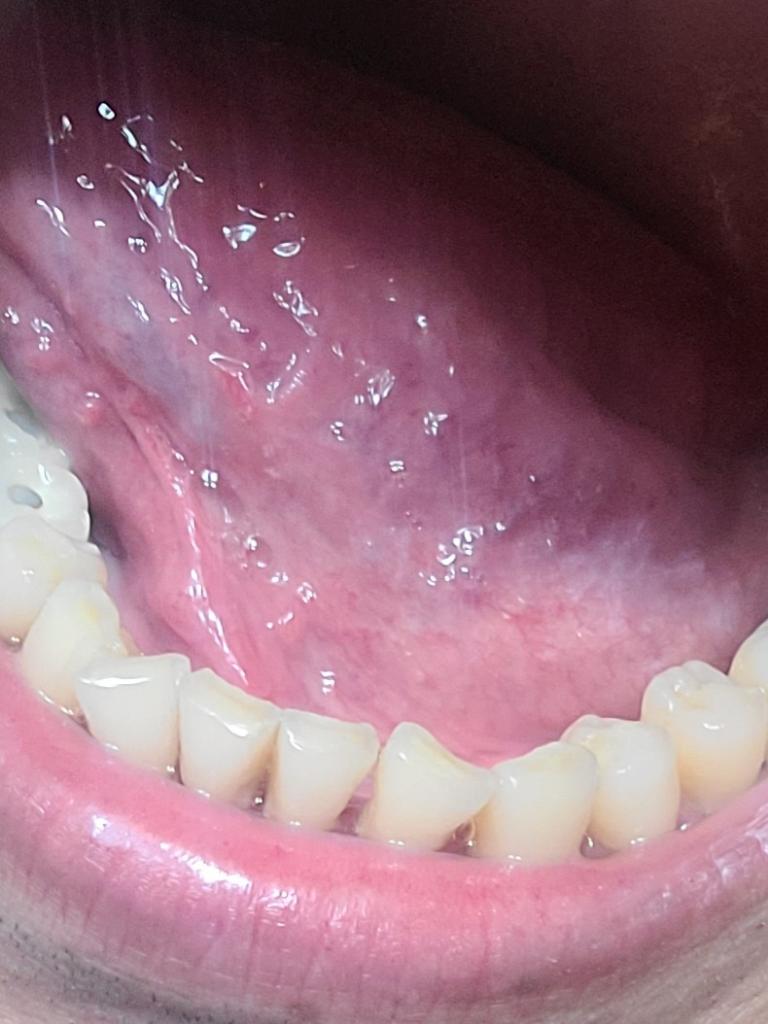

원래 혀 아래가 이런가요? 혀백반증 같은데ㅜㅜ

면역력 저하로 인해서 이렇게 혀아래가 하애지는거 같은데...

혀 백반증은 아니겠죠?ㅜㅜ 너무 걱정됩니다

혀아래가 이렇게 하얘지면 위험한거죠?

보내주신 사진에는 백반증의 소견은 보이지 않으며 정상적인 상태로 보이기 때문에 걱정하지 않으셔도 될 것 같습니다.

백반증의 형태도 아니며 사진상으로 보았을 때는 큰 문제가 되지 않습니다. 해당 부위는 일반인들이 살아가면서 자주 보지 못하다가 우연히 접한 이후에 이상하다고 생각할 수 있는 구조물이 많은 부위입니다. 사진 상에서 전혀 문제가 되지 않으며 통증 및 불편감이 없다면 크게 걱정하지 않으셔도 됩니다.

사진상으로 보면 크게 문제가 있어 보이는거 같진 않습니다. 혀백반증은 회백색의 딱딱한 점막이 혀에 나타나는 증상입니다.

사진으로만 봤을경우에는 큰문제가 없는것으로 보입니다.

혀가 신장이 되면 일시적으로 혈액이 빠지면서 하얗게 보일수 있어요.

정상구조로 보입니다.

구강백반증은 구강내에 하얀반점이 생기는 질환으로 자연치유가 많습니다.